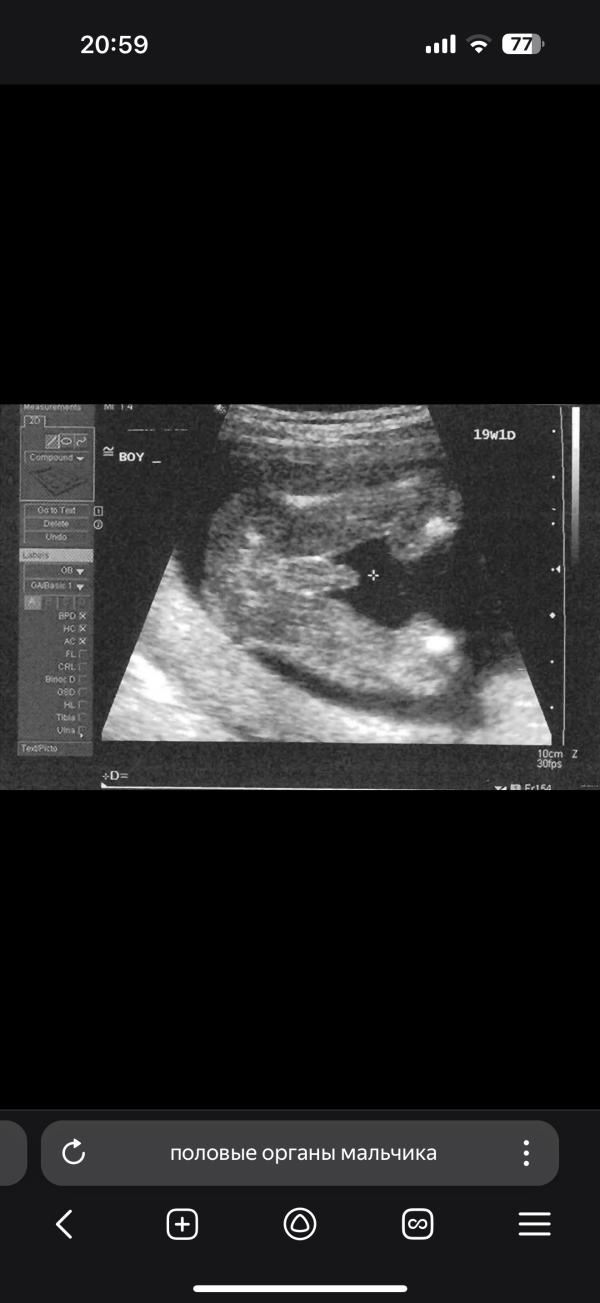

На примере узи покажу. Вот на узи половые органы мальчика вот внизу яичек и между попкой от яичек и до попки у него какое то не понятное уплотнение, полоска такая , я когда подмываю или салфеткоц протираю и касаюсь этого места я поняла что ему больно. К врачу 7 числа. Всем спасибо

Да, этот рубец связан с эмбриональным развитием половых органов у мальчиков. А вот что больно... Странно

Похоже на рубец да. Сегодня мне показалось что воспалилось будто, запереживала из-за этого.

Этот рубец - место сращения.